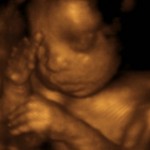

Every so often you hear of pregnancies gone awry. TLC has an entire program dedicated to undiagnosed pregnancies. What if  you were told  the baby died and found out otherwise? One  woman is facing such a dilemma. A British woman was told that she had suffered a miscarriage only to find that her baby was still alive a month later.Catherine Kent, 27, and her partner Kevin Gray, 28, were devastated when they were told in June that their unborn baby had died at eight weeks. She was offered an abortion or pills to shorten the miscarriage, the Daily Mail reported.Kent chose to wait for the baby to pass naturally — and a month later was stunned when a scan revealed that her child was still alive. The couple were elated to learn she was still pregnant, but furious with the hospital for the mistake.”They could have aborted my baby while it was alive,” Kent told the Daily Mail. “How can the hospital make a mistake like that?”Kent is due to give birth to the baby girl in February. The pair have filed a complaint with City Hospitals Sunderland NHS Trust but have yet to hear back. Aren’t There Better Things To Worry About Than Bert & Ernie? [OPINION] EXCLUSIVE: American Idol Alumni Nearly Shot To Death During Robbery